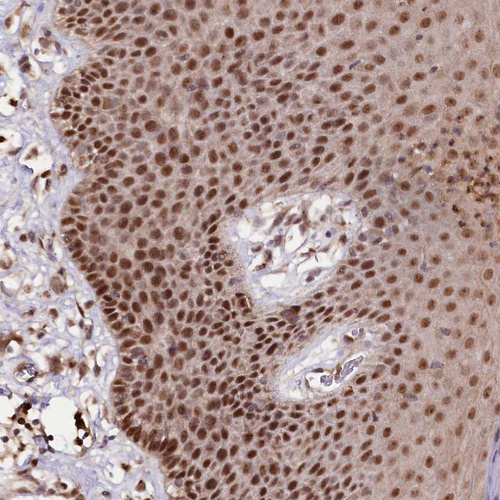

Immunohistochemical staining of human skin shows strong nuclear positivity in squamous epithelial cells.